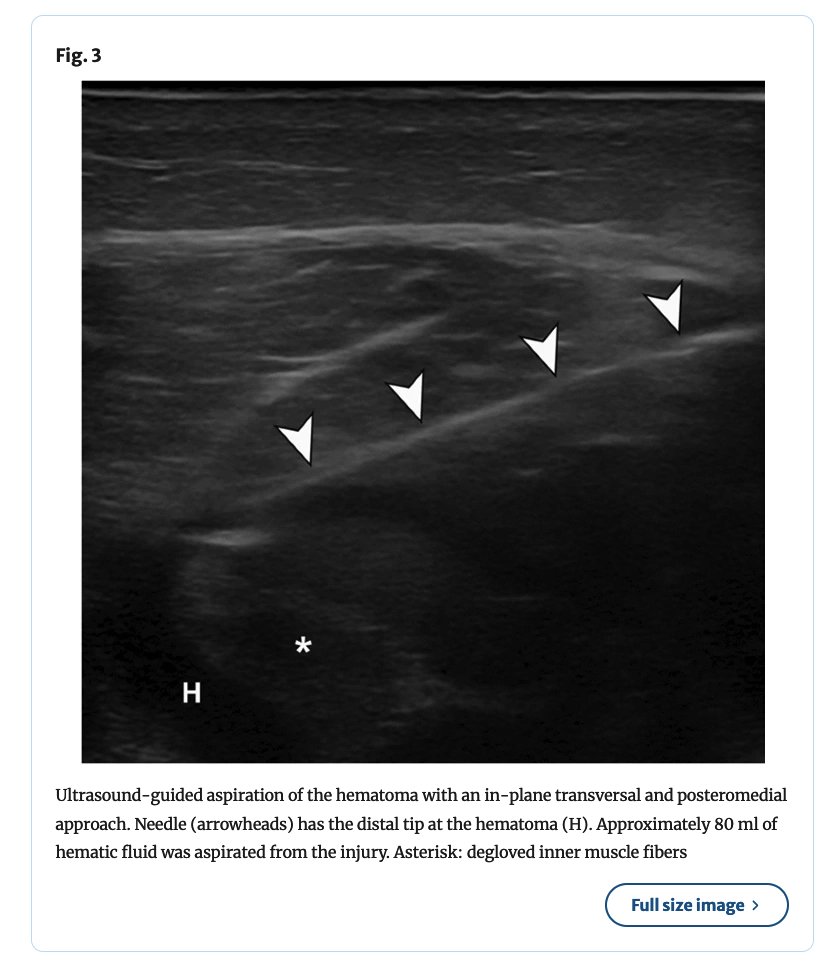

⚽️Degloving intramuscular injuries of the semimembranosus and adductor longus muscles in adolescent soccer players... Degloving muscle injury was described for the rectus femoris where the inner bipennate component is dissociated from its superficial unipennate component. The